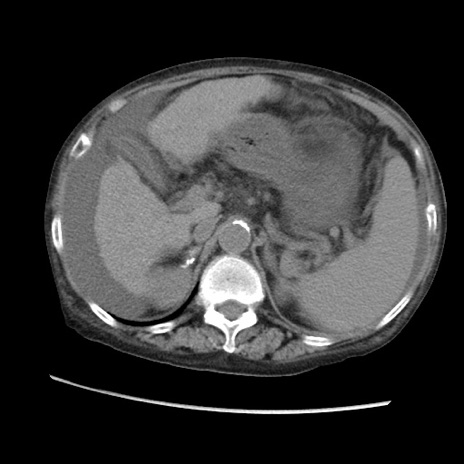

症例31(横断像)

【症例】80歳代 女性

【主訴】腹部膨満感

【現病歴】他院にて肝硬変にてフォロー中。1週間前から便秘、腹部膨満感、臍部腫瘤あり受診となる。

【既往歴】肝硬変

【身体所見】腹部膨隆あり、皮膚変化なし、疼痛なし。

【データ】WBC 4600、CRP 0.25